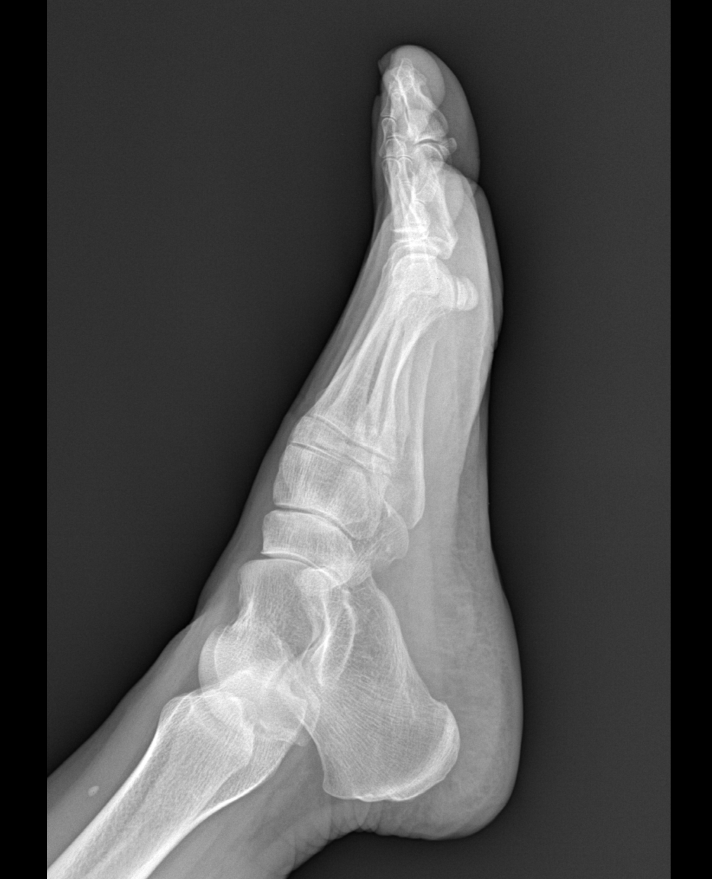

환자분의 x-ray 사진입니다.

x-ray 상에서는 석회화나 다른 특별한 소견은 관찰되지는 않습니다.